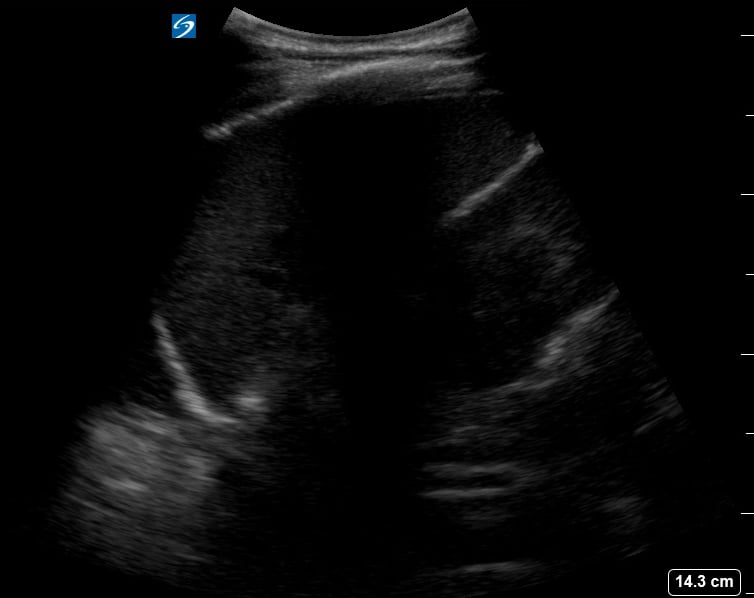

Pleural effusion in pediatrics refers to the abnormal accumulation of fluid in the pleural space, the area between the lungs and chest wall. In pediatric ultrasound, this condition is critical to diagnose, as it can indicate underlying issues like pneumonia, heart failure, or malignancy. Early and accurate detection through ultrasound is crucial for guiding treatment and improving outcomes in children.

Pediatric ultrasound is a highly effective, non-invasive tool for visualizing pleural effusions, offering real-time imaging without radiation exposure. Sonographers can assess the size, character, and location of the fluid, aiding in differentiation from other lung pathologies. Understanding the sonographic appearance of pediatric pleural effusions is essential for medical professionals for precise diagnosis and management.